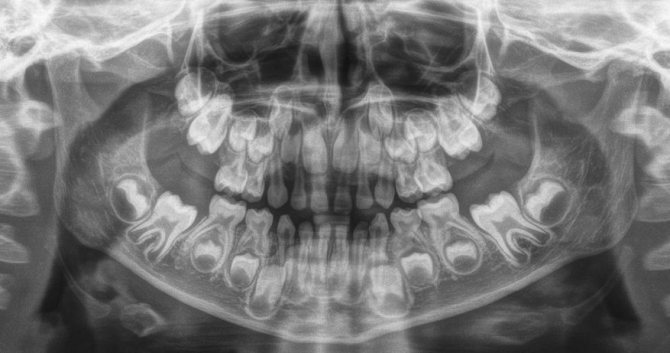

Внимание! Дело в том, что постоянные зубы прорезаются только после выпадения молочных, а до того времени они «сидят» в твёрдых тканях челюсти, что можно увидеть на рентгеновских снимках.